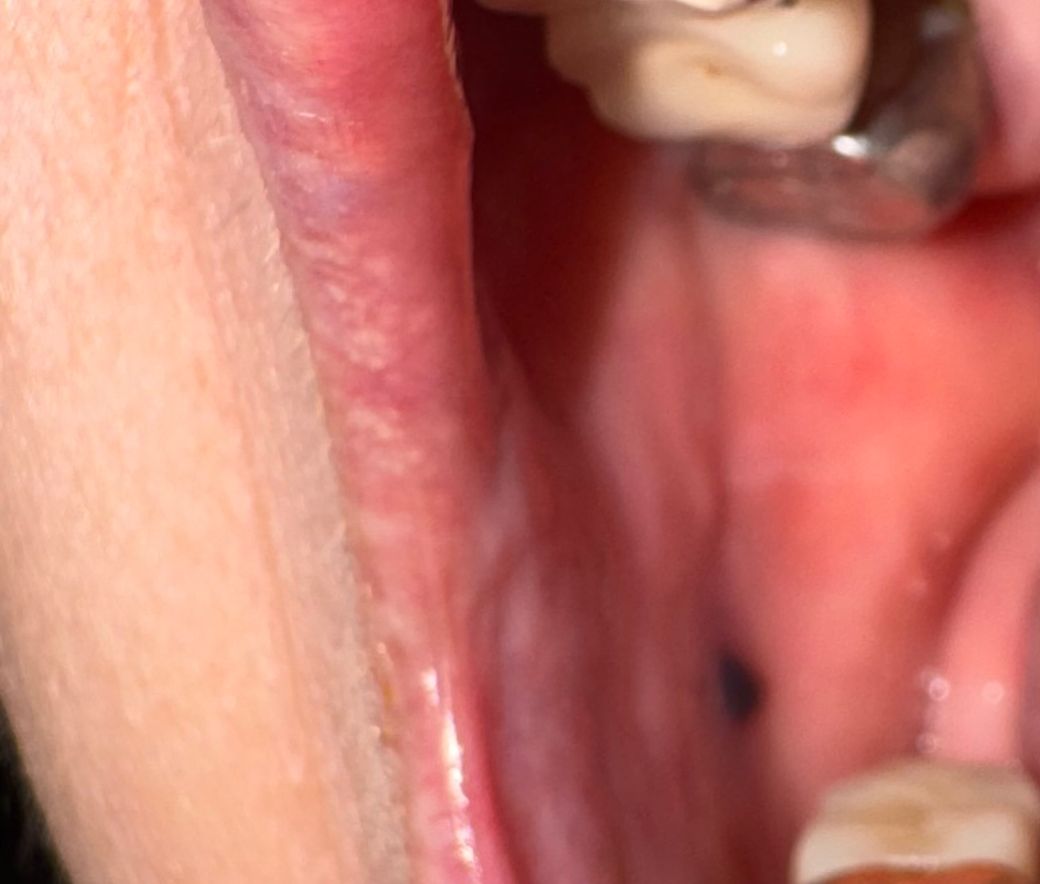

어머니가 오늘 볼안쪽이 부풀어 올랏다가(부엇다가)

어느순간 오후에 가라앉고 따로 통증같은거 없다고 하시는데

입안쪽을보니 사진속처럼 검정점?같은게 볼안쪽에

보이는데 가끔 잇몸을 씹으실때가 있다고 하시는데

볼안쪽에 상처일까요?

구강 내 혈종이 잡힌 것 같은데 볼을 씹으면 그렇게 생길 수 있습니다 치과가서 째고 피 뺄 수 있습니다

볼을 씹어서 상처가 난 흔적인것같습니다. 시간이 경과하면 호전되는 경우가 많으니 지켜봐도 괜찮을것같습니다. 건강하세요.